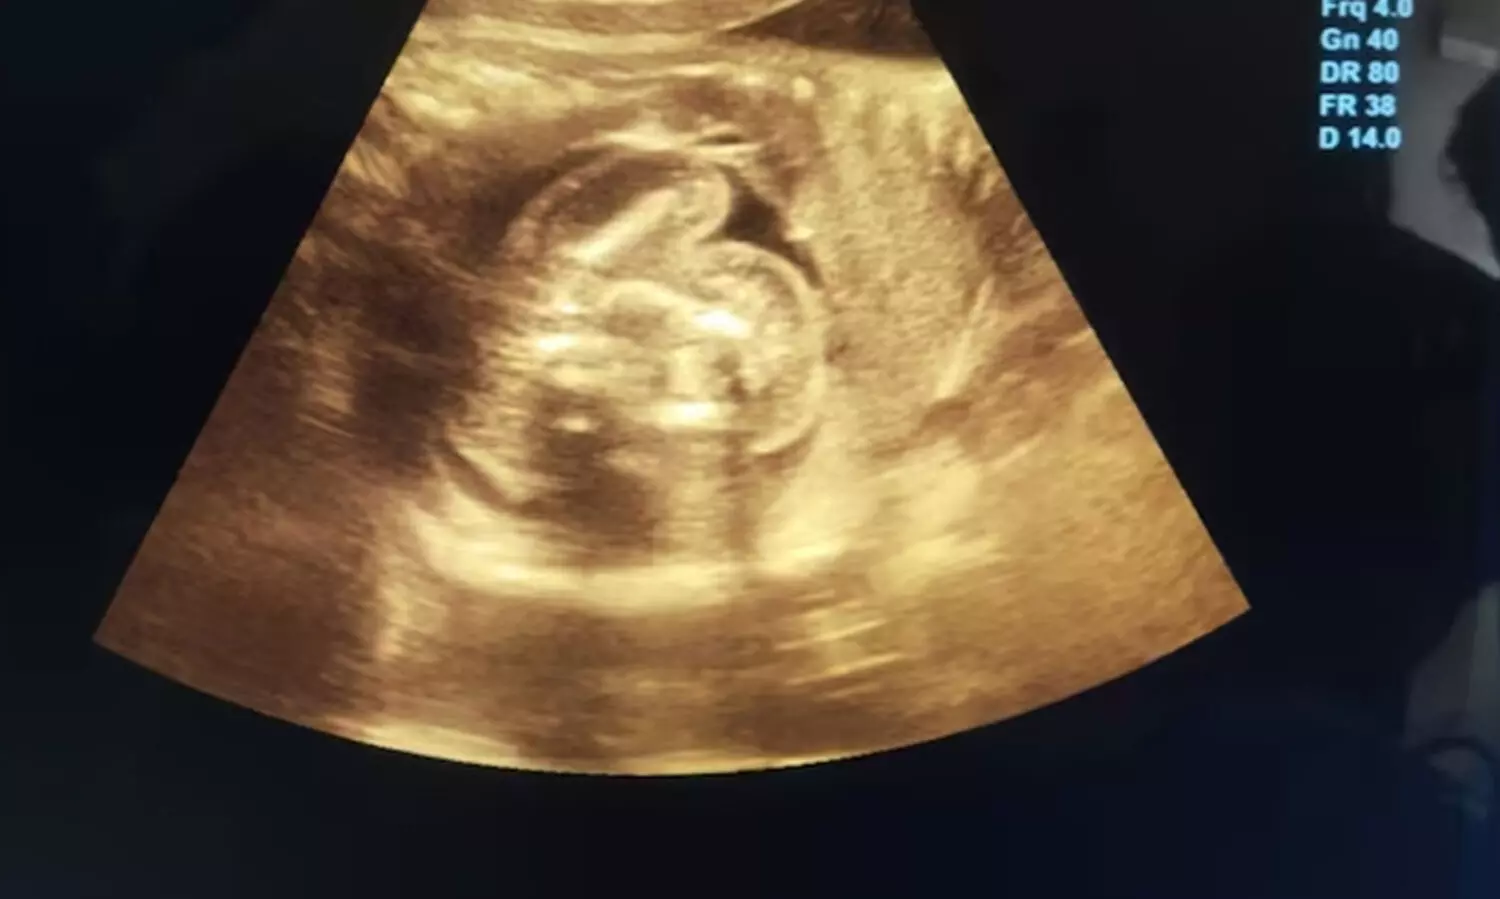

മഹാരാഷ്ട്രയിലെ ഗവ. ആശുപത്രിയിൽ നടത്തിയ സോണോഗ്രാം പരിശോധനയിലാണ് ഒമ്പത് മാസം ഗർഭിണിയായ 32കാരിയുടെ വയറിനുള്ളിൽ വളരുന്ന ഭ്രൂണത്തിനുള്ളിൽ മറ്റൊരു ഭ്രൂണം വളരുന്നത് കണ്ടെത്തിയത്. സോണോഗ്രാം റിപ്പോർട്ടിൽ ഭ്രൂണവളർച്ചയിൽ അപാകത കണ്ട് വിശദമായി പരിശോധിച്ചപ്പോഴാണ് ഇത്തരത്തിലുള്ള അപൂർവ കേസാണെന്ന് കണ്ടെത്തിയതെന്ന് ഗൈനക്കോളജിസ്റ്റ് ഡോ. പ്രസാദ് അഗർവാൾ പറഞ്ഞു.